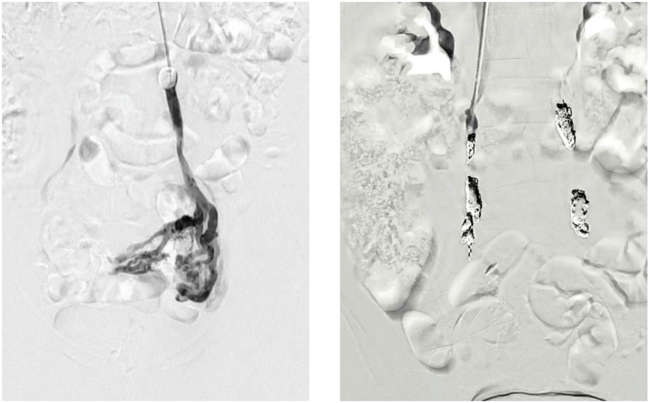

Winokur-Fig1-CLD-MarchApril 2026

Figure 1. Pre and post pelvic vein embolization.

What’s happening is that enlarged veins develop in the pelvis around the uterus or ovaries, which can lead to chronic pelvic pain. A lot of it relates to venous reflux, leading to “backup” in the ovarian and pelvic veins, very similar to varicose veins in the legs. The frustrating part has been that we’ve had good treatment options with pelvic vein embolization, but it has never really had a randomized controlled trial behind it, so physicians have been hesitant in adoption.

From a procedural standpoint, the left ovarian vein is often dilated and stretched so the valves can’t close. From there, we can go down the inferior vena cava into the left renal vein, and then down the left ovarian vein into the pelvis. We inject sclerosis medication into the dilated pelvic veins that are driving symptoms, and we place coils in the ovarian vein.

Then we come back and treat the right side with coils as well, so we are embolizing and addressing the whole pelvic venous network bilaterally.